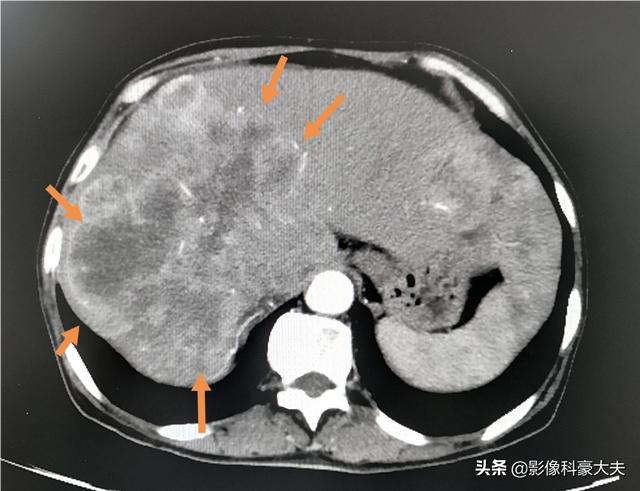

Multiple riesige Lebermetastasen wie diese können in kurzer Zeit fortschreiten, wenn sie unkontrolliert oder unempfindlich gegenüber einer Behandlung bleiben.